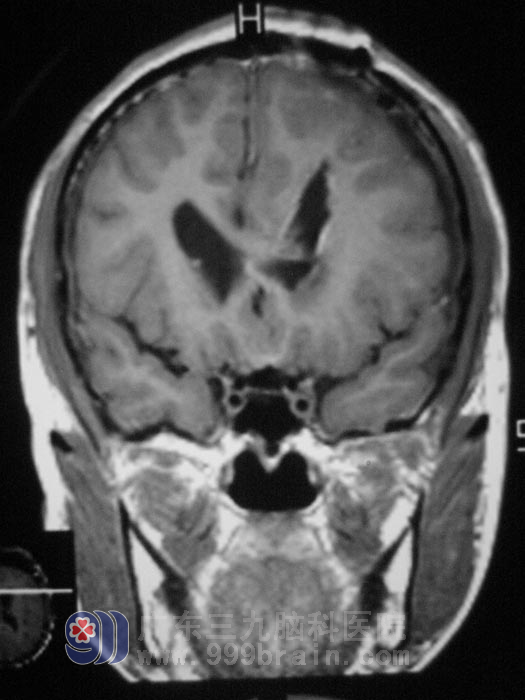

得知儿子得了脑肿瘤,一家人带着小何到处求医,想着儿子风华正茂的年纪,说什么也不能放弃。几经周折,妈妈带着儿子来到广东三九脑科医院找到鲁明主任,门诊查头部MRI报双侧脑室占位性病变,伴梗阻性脑积水。粗侧视力左眼1.0,视野正常,右眼0.3,视野较左眼缩小,左耳听力减退,完善相关检查后,4月21日在全麻下行双侧侧脑室占位切除术,见脑室内灰黄色肿瘤,质中偏软、鱼肉样,内有钙化结节,血运较丰富,显微镜下分块切除肿瘤,肿瘤左侧达左侧丘脑,边界不甚清楚,与脑室壁粘连,内侧至对侧脑室,显微镜下基本全切除肿瘤,手术过程顺利,术后复查CT未见异常,经过一段时间的住院治疗,小何已经康复出院,术后病理结果为:(脑室内)星形胶质细胞瘤,WHOII级。小何后续仍需要行进一步的放疗。http://www.999brain.com/

手术后